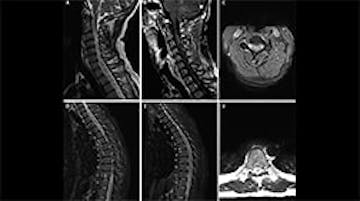

GFAP Levels Correlated With Clinical and MRI Outcomes in Individuals with Relapsing Multiple Sclerosis

MRI-Guided Treatment Escalation May Reduce Relapse Risk in Stable MS Patients